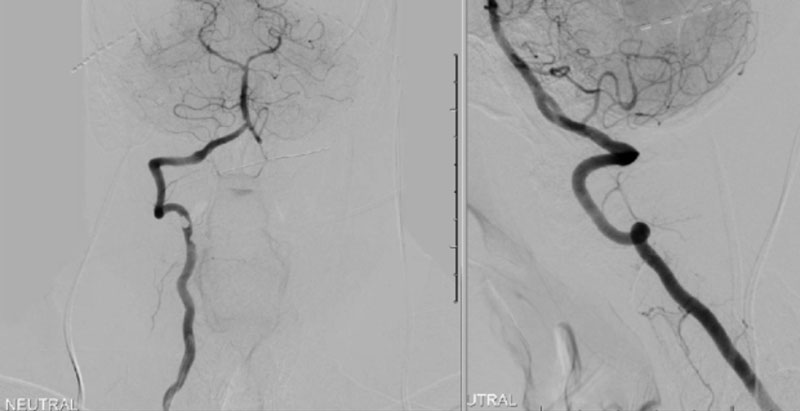

The patient was brought to the operating room, and general tracheal anesthesia was initiated via fiberoptic approach. Somatosensory potentials, motor evoked potentials, and brainstem auditory evoked responses were recorded. The patient then underwent intraoperative angiography of the right Vertebral Artery performed via a 5 French Right Radial Artery access. Once it was established that he had good flow, a Mayfield head holder was attached to the patient’s head on the 60 pounds of torque pressure. The Wilson frame attached to the Jackson table was then placed on top the patient attached to the Jackson frame. The patient was secured with straps and bed sheets and then positioned prone by rotating the frame around its axis. The flat plate of the Jackson table was then removed, and the patient bony prominences and soft tissues were adequately padded. Angiography was then again repeated showing good flow through the Vertebral Artery. After that, after being properly secured to the table with access to the right radial sheath, the neck and the left posterior iliac crest area and a tricortical autograft was then obtained with osteotomes. Iliac crest was reconstructed with fiber graft allograft. Posterior cervical incision was then performed and the spinous processes of C2 and C3 were identified and cleared of the fascia and then the muscle the way to the lateral edges of lateral masses. The C1 posterior ring was completely subluxed under the occiput and C2 lamina. The patient evoked potentials remained stable. The C1 lamina was then cleared of the soft tissue laterally on both sides. On the left side, significant osteophyte formation was visualized, and the C1-2 foramen was completely closed by the bone. On the right side, the C1-2 foramen was dissected, and the veins were coagulated with bipolar cautery. The C2 nerve root was identified and then coagulated bipolar cautery and divided with micro scissors, completing the planned C2 rhizotomy. The decision was made to perform an occiput to C3 fusion, since the articulation between the occiput, C1, and C2 was technically difficult and most likely would result in an inadequate fixation. At that point, a small occipital plate was brought into the field, and secured to the suboccipital bone with 14- and 12-mm screws. Then a pilot hold was created into the lateral masses of C3 bilaterally. The C3 appeared to be solidly fused to C2. First a hole was made with the drill and then passes were made with 40 mm drill with the guide. There were palpated with a ball-tipped probe and tapped. After the replaced 14 mm lateral mass screws into the lateral masses of C3 bilaterally. After the rods were fashioned and secured to the screw heads and the occipital plate with locking caps. (Figure 6)

Intraoperative angiography was then repeated again, showing good flow through the right Vertebral Artery into the Basilar Artery. Intraoperative fluoroscopy was then also performed to confirm good position of the screws and rods in both AP and lateral projections. (Figure 7)